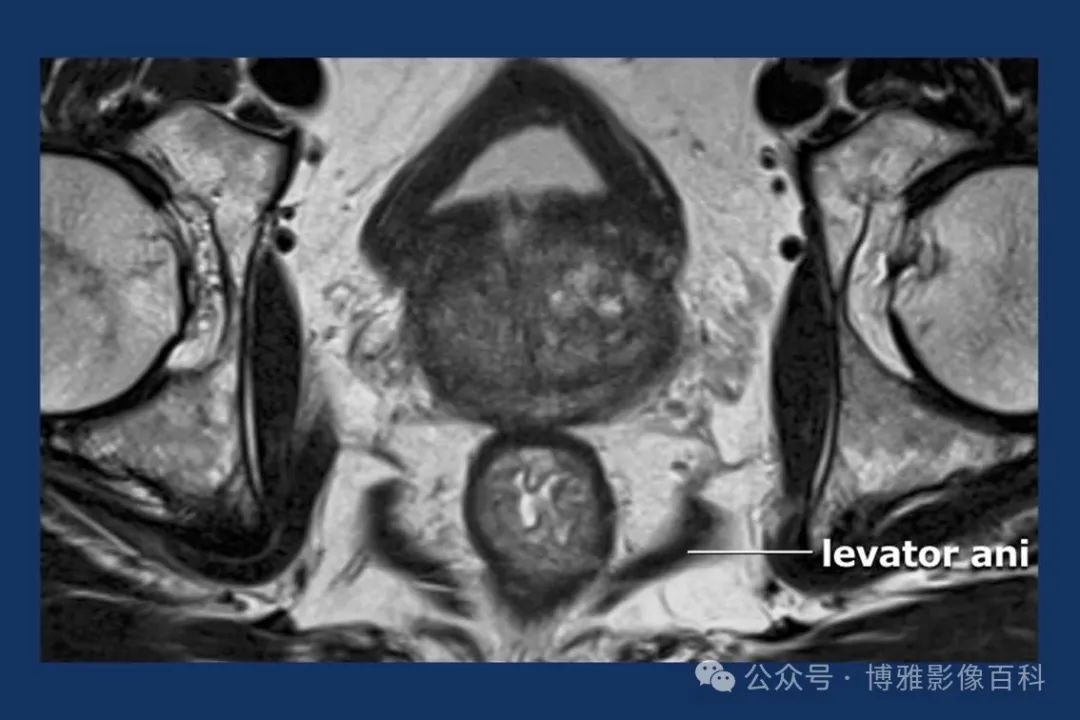

MR 解剖学

前列腺良性增生患者的轴向T2 图像,其他方面正常。外周带是一薄层均匀的高信号,边界清晰连续性的低信号包膜。移行带通常表现为不均匀中等信号,病灶被边界清楚的BPH良性前列腺增生结节所取代。精囊具有均匀T2高信号。未见淋巴结肿大。